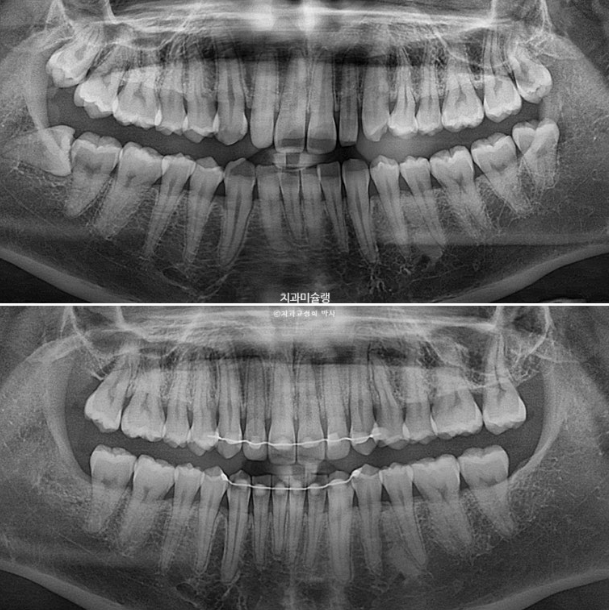

2022.10~2025.04

2년 반의 기간동안 치근흡수는 없고 편측 어금니는 계획대로 사랑니 공간으로 잘 이동했습니다.

치근평행도는 좋습니다.